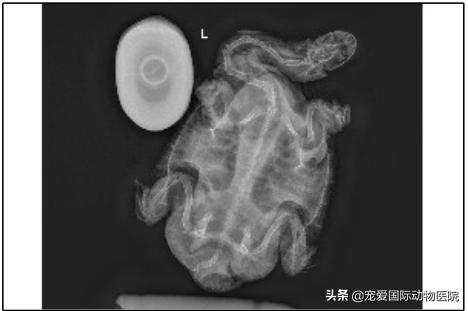

影像学检查:

胸腹腔左侧位

胸腹腔头尾位

胸腹腔背腹位